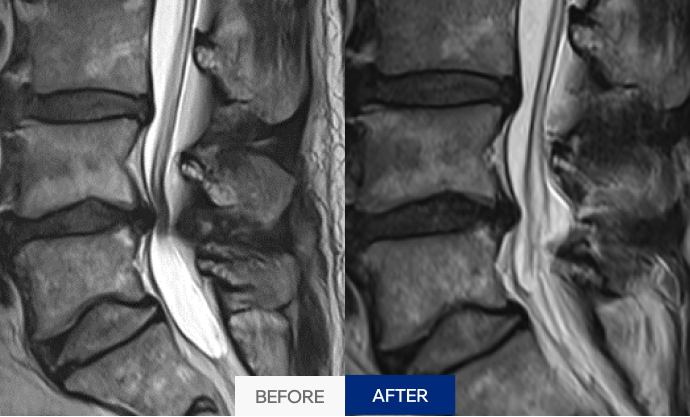

척추 뼈 사이에 있는 연골(디스크)이 탈출해 신경을 압박하면서

허리 통증, 다리 저림, 감각 이상 등을 유발하는 질환입니다.